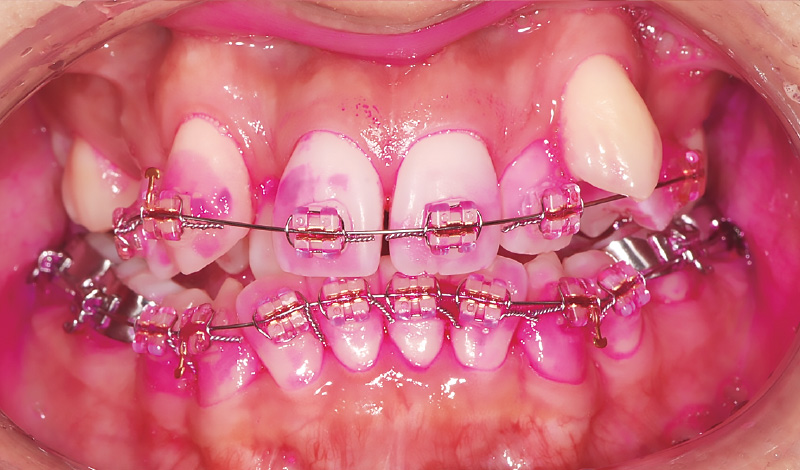

症例1-1 インビザライン矯正中の30代女性。アタッチメントを装着していることもあり、プラークコントロールに苦戦していた。 -

症例1-2 「ソニッケアー」導入後の歯面のプラークの付着状態(「ソニッケアー」によるブラッシング前)。導入前よりもプラークの付着量が減少。 -